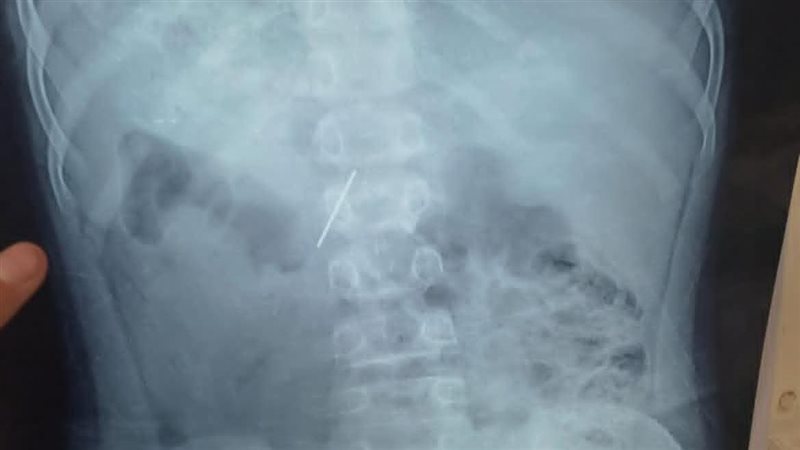

نجح قسم جراحة الأطفال بمستشفى الأطفال التخصصي في بنها، في استخراج مسمار دباسة كراسة اخترق جدار بطن طفل واستقر داخل التجويف البطني، بعد تدخّل جراحي متقدّم جمع بين المنظار وجهاز السي أرم لتحديد الموقع بدقة متناهية.

وقاد الفريق الطبي بمستشفى الأطفال التخصصي في بنها، العملية بامتياز تحت إشراف الدكتور محمد متولي، رئيس قسم جراحة الأطفال، ووليد محمد، استشاري جراحة، ومحمود ممدوح، نائب قسم الجراحة، حيث تم توظيف المنظار الجراحي؛ لتقليل آثار الجراحة والشفاء السريع، فيما لعب جهاز الـ«سي أرم» دور الخريطة الحية لتحديد موقع المسمار بدقة مدهشة، ما حول العملية إلى مزيج من مهارة الجراح وذكاء الأجهزة.